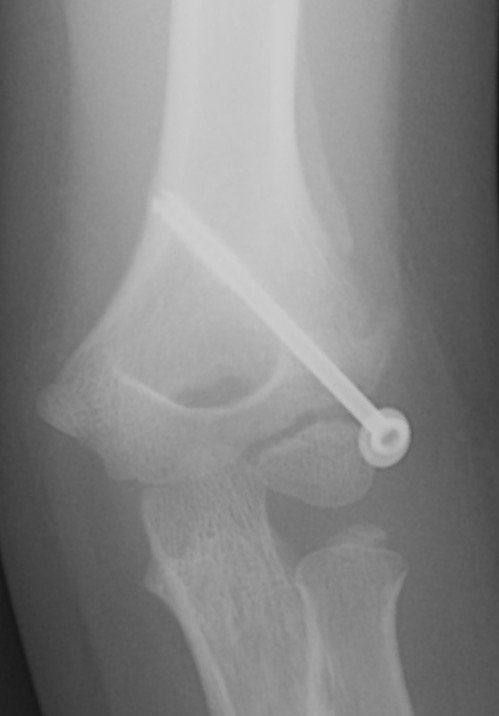

1. Closed reduction and percutaneous K wires

Closed reduction and percutaneous K wires

Indications

- residual displacement < 2 mm

- no rotation

- confirm joint surface anatomically reduced (arthrogram)

Technique

- reduce by extension and varus

- pronation uses flexor mass to pull lateral condyle forward

- percutaneous K wire